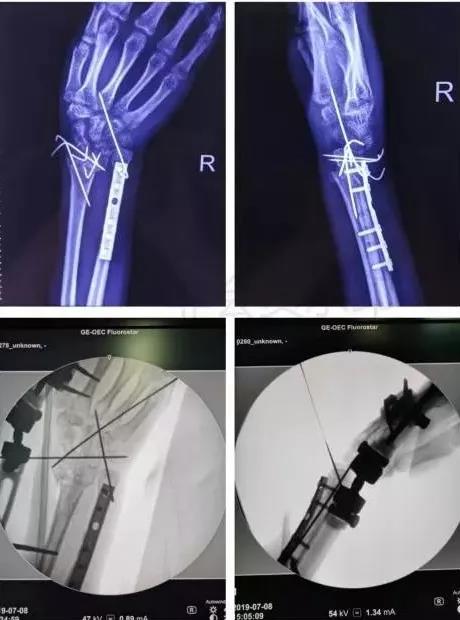

7)手部骨折

- 无论闭合或开放性骨折,均应早期复位内固定。

- 合并神经,血管,肌腱损伤,紧急手术。